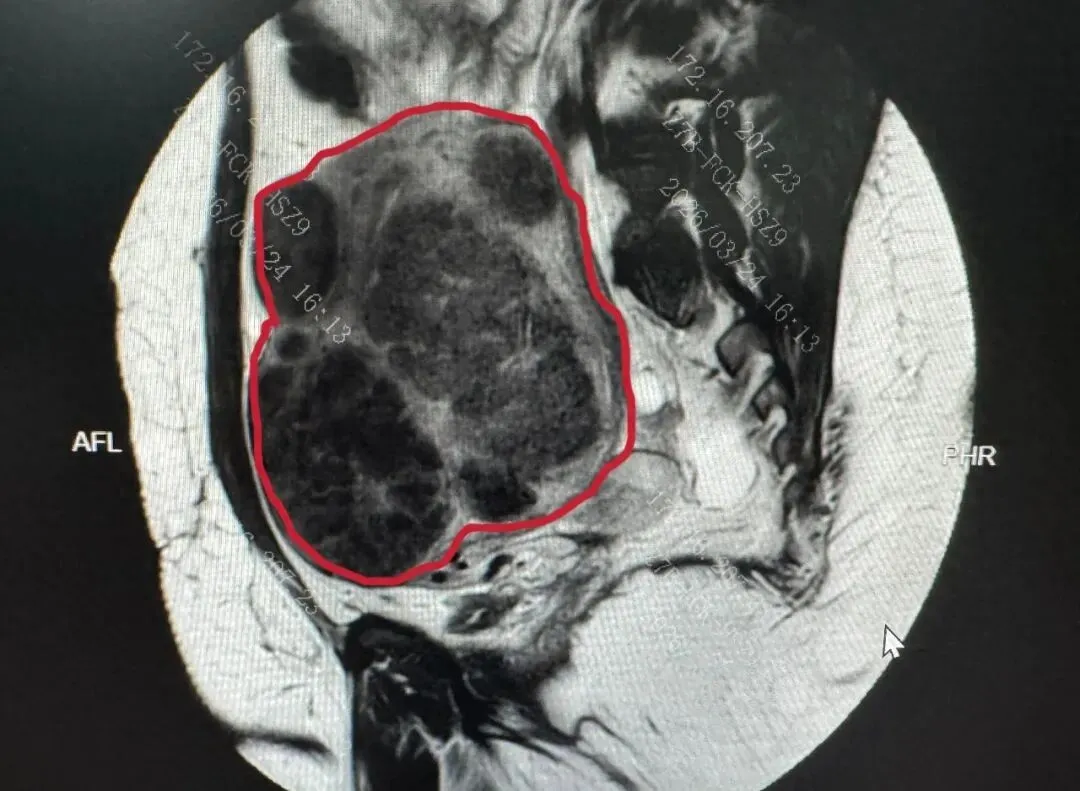

图示 PUSH 术前 MRI 子宫图像(红色线内区域为子宫)及子宫内弥漫存在的肌瘤影

体重 216 斤,臀围 128cm,皮下脂肪很厚,手术视野极差;未怀孕,子宫却被撑到怀孕 4 个月大小,形态完全失常;肌瘤弥漫性生长,数量无法预估,最大直径超 10cm,最小的肉眼几乎不可见;既往有在腹腔镜下剥肌瘤并大出血的手术史,腹腔粘连情况复杂。

更重要的是,安娜保宫、保生育的意愿极其强烈,手术不仅要剔净所有可见瘤体,还要最大限度保护正常子宫肌层,为未来生育留下足够空间。